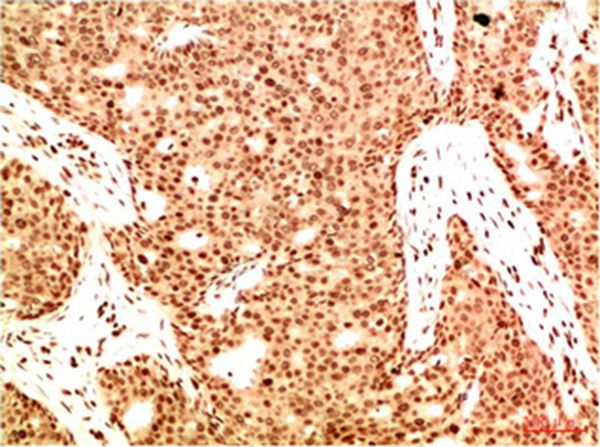

Immunohistochemical analysis of paraffin-embedded Human Breast Carcinoma Tissue using Acetyl NF kB P65(K314/K315) Mouse mAb diluted at 1:200.